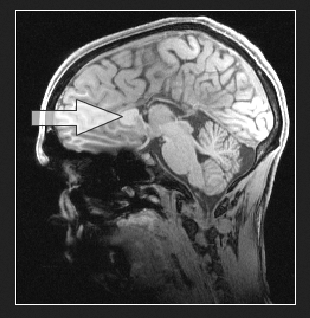

Partial AgCC – The arrow points to the part of the corpus callosum that developed.

If the corpus callosum forms but is unusually thin, it is labeled corpus callosum ‘hypogenesis' or ‘hypoplasia.'